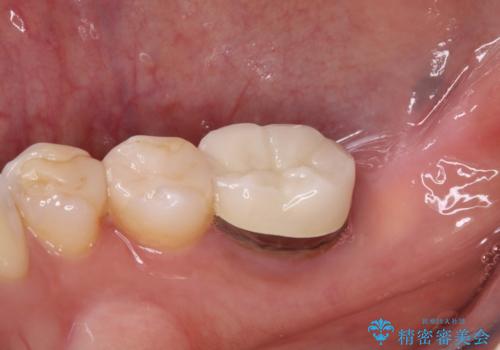

放置した奥歯 部分矯正を併用したインプラント補綴治療

- 右下欠損部のインプラント治療を希望して来院された患者様です。

右下の欠損部を長期間欠損を放置していたことで、咬み合う上の奥歯が動いてしまっていたので、まずは上顎奥歯の部分矯正を行うこととしました。

理想的な咬み合わせに改善した上で、インプラント補綴治療を行うこととしました。

部分矯正を行ったこと治療期間は長くなりましたが、違和感のない咬み合わせを達成することができました。